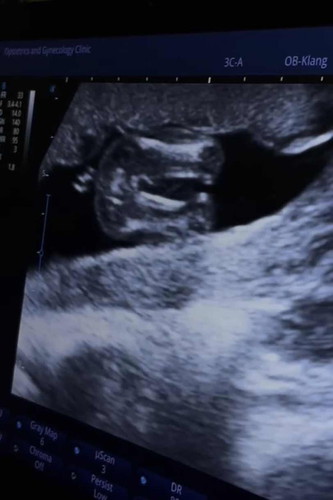

น้องเป็นเพศอะไรคะ

แม่ๆช่วยดูหน่อยค่ะ แม่ไม่ค่อยชัวร์ อยากได้ลูกสาวกลัวคิดไปเอง😂😂

บ้านนี้คุณหมอยืนยันว่าเป็นหญิงชัวร์ค่ะ ขอให้สมหวังนะคะแม่